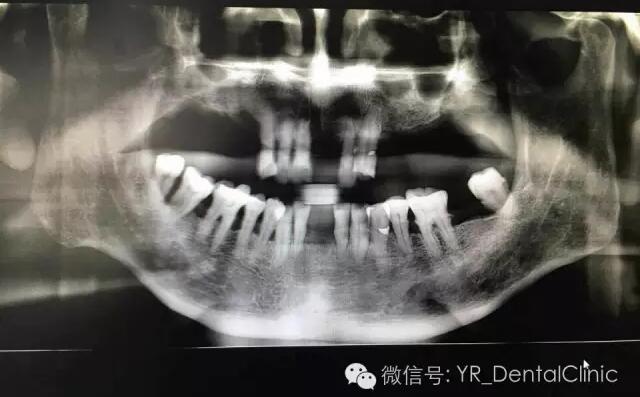

种植前全景片